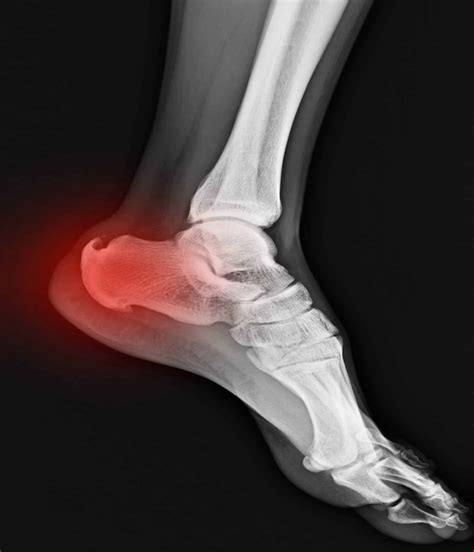

Diagnosing Achilles Calcaneal Spur

Diagnosing Achilles Calcaneal Spur typically involves a combination of a physical examination and imaging tests. A healthcare provider will:

• Examine the foot and heel for signs of inflammation and tenderness.

• Review the patient's medical history and symptoms.

• Order imaging tests, such as X-rays, to confirm the presence of a heel spur.

In some cases, additional tests such as MRI or ultrasound may be recommended to assess the extent of the inflammation and damage to the plantar fascia.